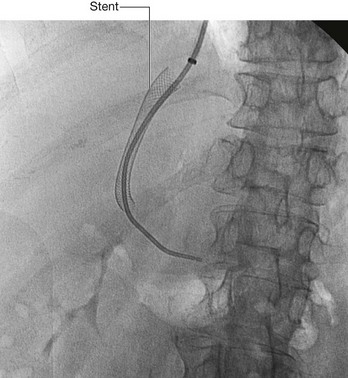

Nephrostomy

A nephrostomy is a procedure where a tube is placed through the lateral or posterior abdominal wall into the renal cortex to lie within the renal pelvis. The function of this tube is to allow drainage of urine from the renal pelvis through the tube externally (Fig. 4.145).

image

Fig. 4.145 This radiograph, anterior-posterior view, demonstrates a double J stent. The superior aspect of the double J stent is situated within the renal pelvis. The stent passes through the ureter describing the path of the ureter, and the tip of the double J stent is projected over the bladder, which appears as a slightly dense area on the radiograph.

The kidneys are situated on the posterior abdominal wall, and in thin healthy subjects may be only up to 2–3 cm from the skin. Access to the kidney is relatively straightforward, because the kidney can be easily visualized under ultrasound guidance. Using local anesthetic, a needle can be placed, under ultrasound direction, through the skin into the renal cortex and into the renal pelvis. A series of wires and tubes can be passed through the needle to position the drainage catheter.

The indications of such a procedure are many. In patients with distal ureteric obstruction the back pressure of urine within the ureters and the kidney significantly impairs the function of the kidney, which will fail to function. This will produce renal failure and ultimately death. Furthermore, a dilated obstructed system is also susceptible to infection. In many cases, there is not only obstruction producing renal failure but also infected urine within the system.

Page 364